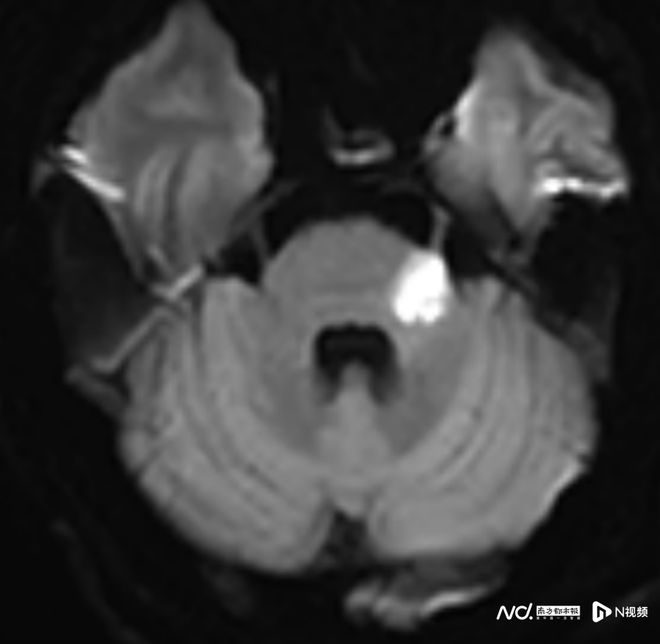

相反,59歲的趙叔在冠脈支架術后出現頭暈、行走不穩,卻拖延至十天后因摔倒才就醫,錯過了最佳治療窗口,最終留下行走不穩的后遺癥,需長期康復。